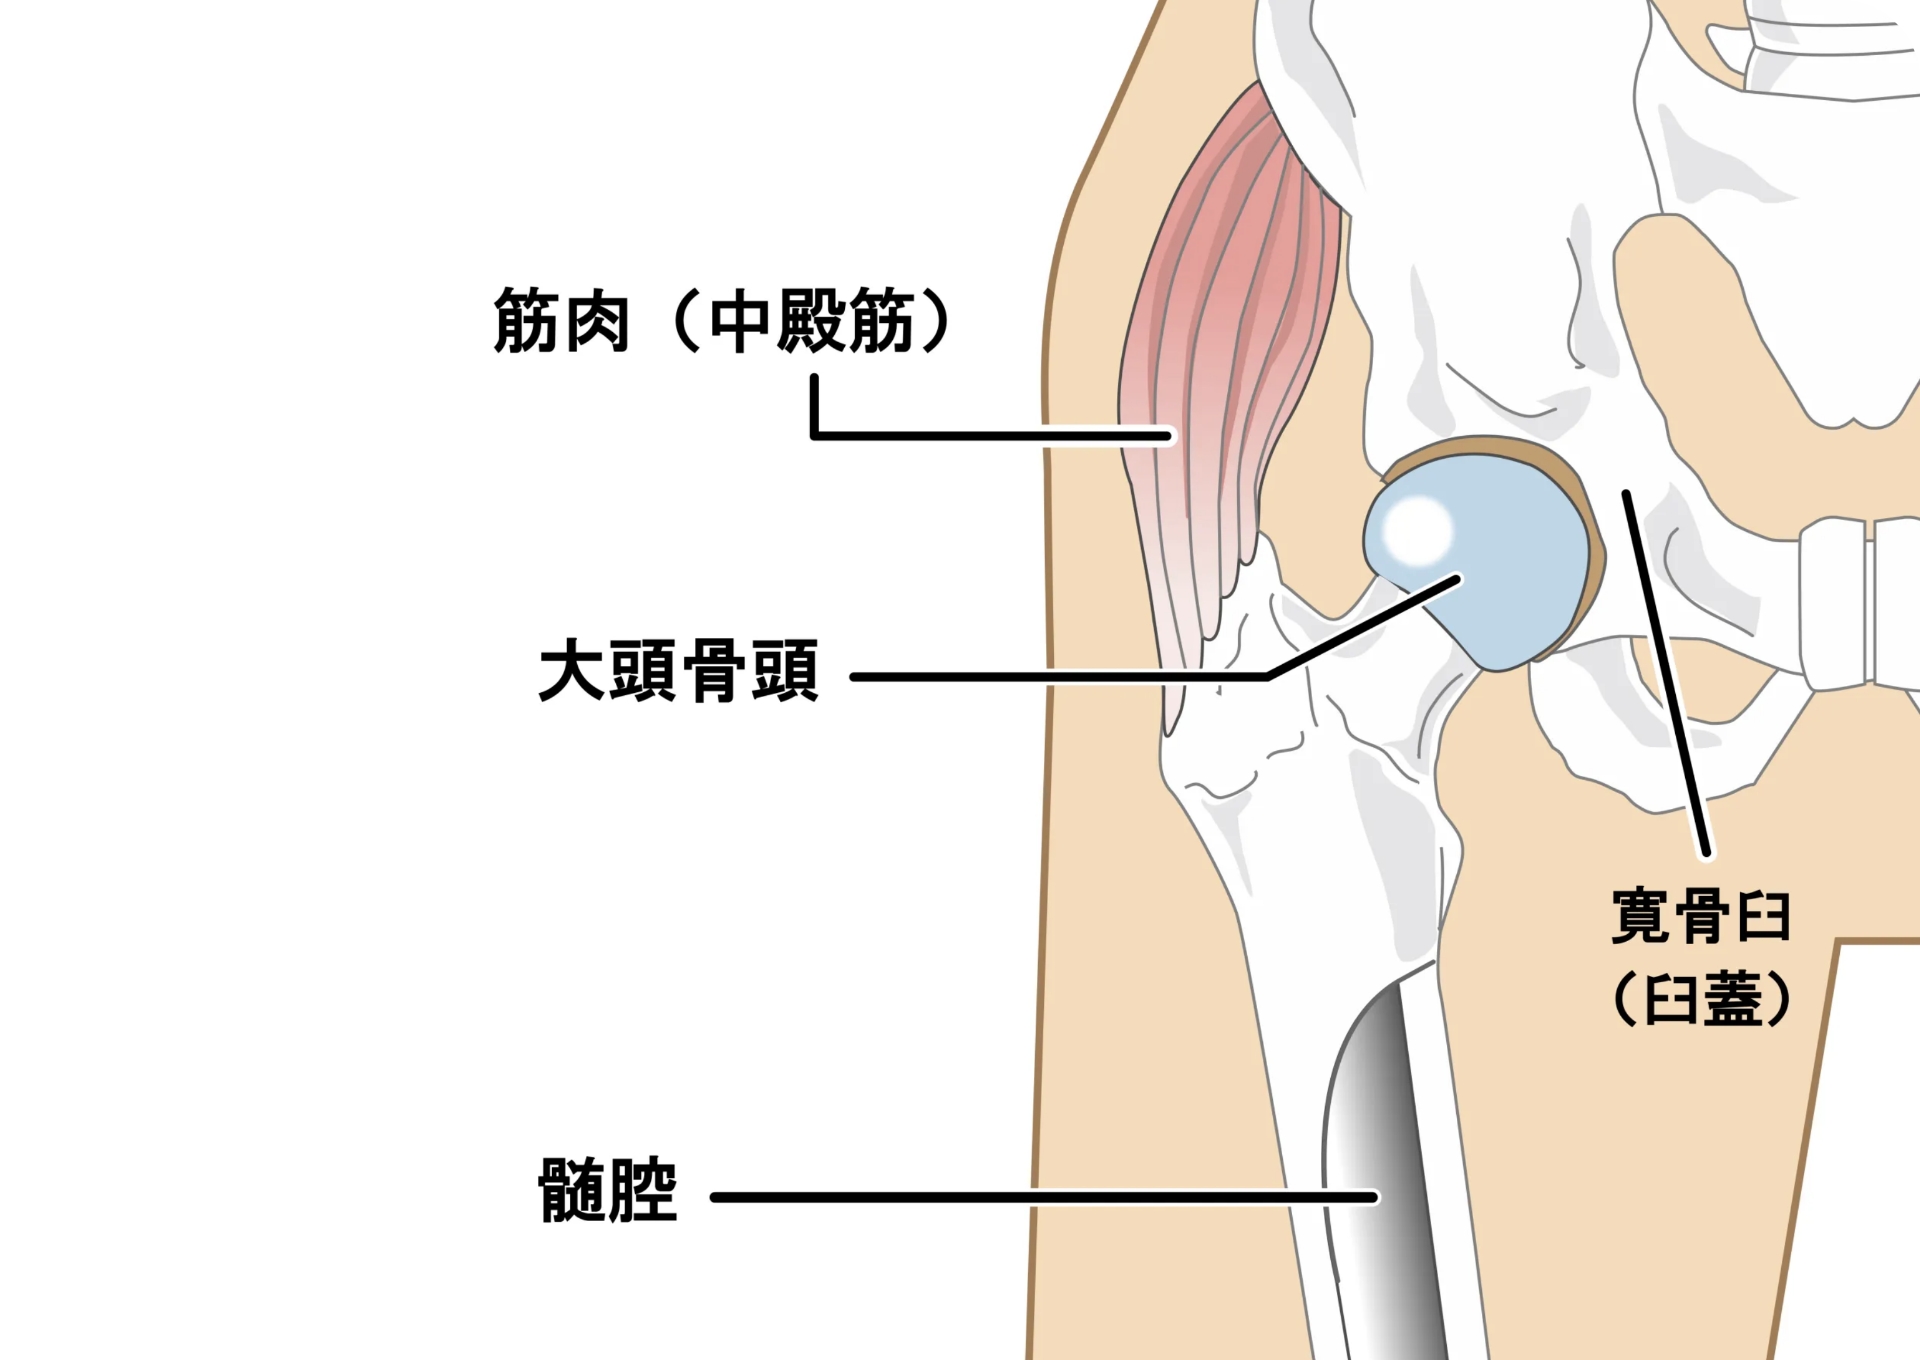

主な原因は幼少期の「発育不全」や「臼蓋形成不全(きゅうがいけいせいふぜん)」と呼ばれる生まれつきの関節の異常によるものが多いとされています。また、荷重がかかる関節のため、加齢やホルモンバランスの変化によって徐々に変形がみられ、自然に関節が変形して発症することもあります。

初期は足の付け根の違和感程度ですが、徐々に痛みや運動制限がみられ、症状によっては股関節ごと人工のものに置き換えるなどの大掛かりな手術が適応になることがあります。